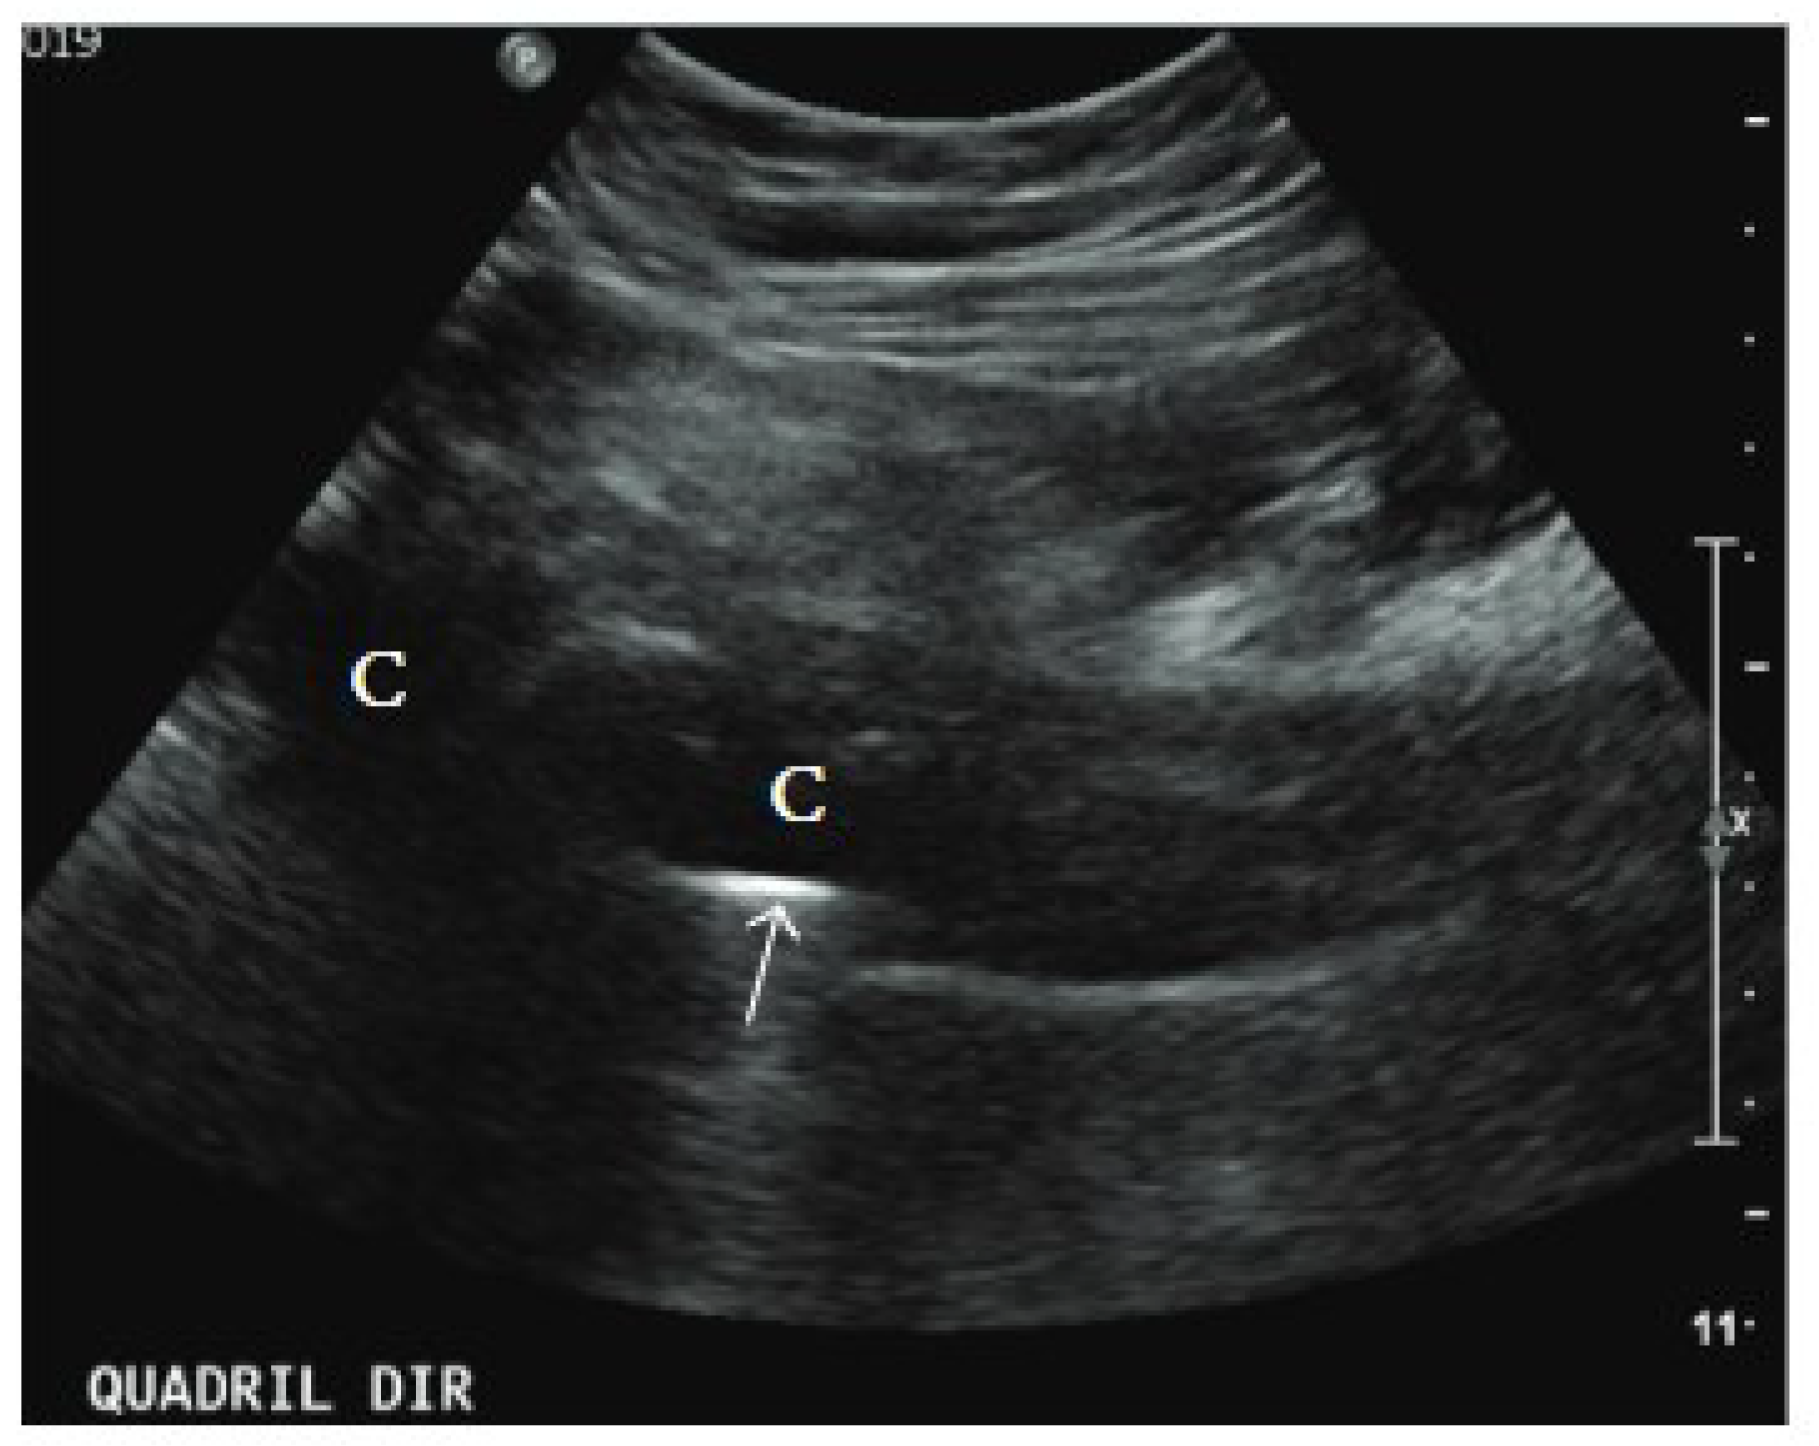

4.2. Ultrasound

- Nyamankolly, E.; Leitao, J.; Lescure, M.; Shipley, E.; Mazé, J.; Desclaux, A.; Dutronc, H.; Neau, D.; Dauchy, F.-A. Ultrasonography performed by an infectiologist in hip and knee prosthetic joint and native joint infections. Infect. Dis. Now. 2023, 53, 104689. [Google Scholar] [CrossRef]

- Wei, W.; Huang, X.; Huang, L.; Xie, L.; Li, W.; Gong, Y.; Chen, S. Application of Ultrasound in Diagnosis of Prosthesis Loosening and Infection After Total Hip Arthroplasty. Res. Sq. 2021; preprint. [Google Scholar]

- Abbas, H.M.; Maged, A.M.; Elshewi, E. Role of Ultrasonography in Prosthetic Joint Infection Diagnosis and Assessment. Med. J. Cairo Univ. 2022, 90, 1633–1642. [Google Scholar] [CrossRef]

- Bengtzen, R.R.; Lee, J. Point-of-Care ultrasound and the septic prosthetic hip joint. J. Emerg. Med. 2019, 57, 701–704. [Google Scholar] [CrossRef] [PubMed]